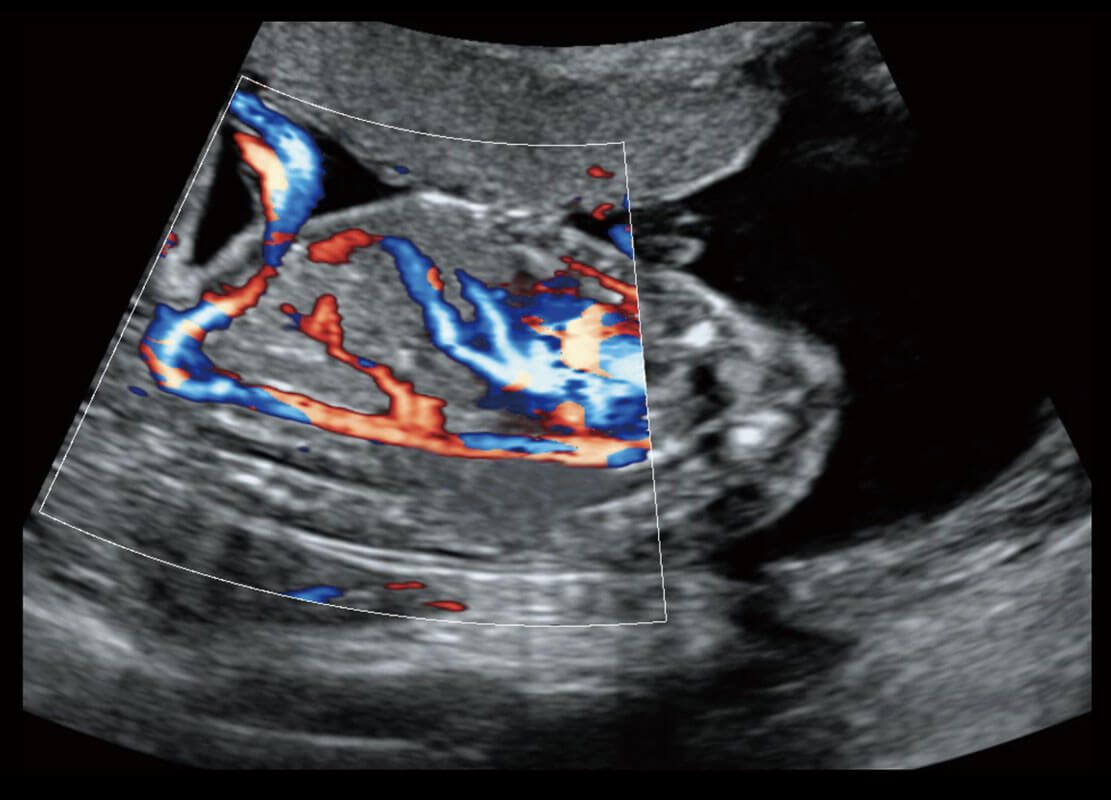

胎心筛查

P60搭载一系列胎儿心脏成像技术,实现精细的胎儿心脏评估。

• 四腔切面

• 四腔心血流

• 右室双出口

• 胎心容积成像